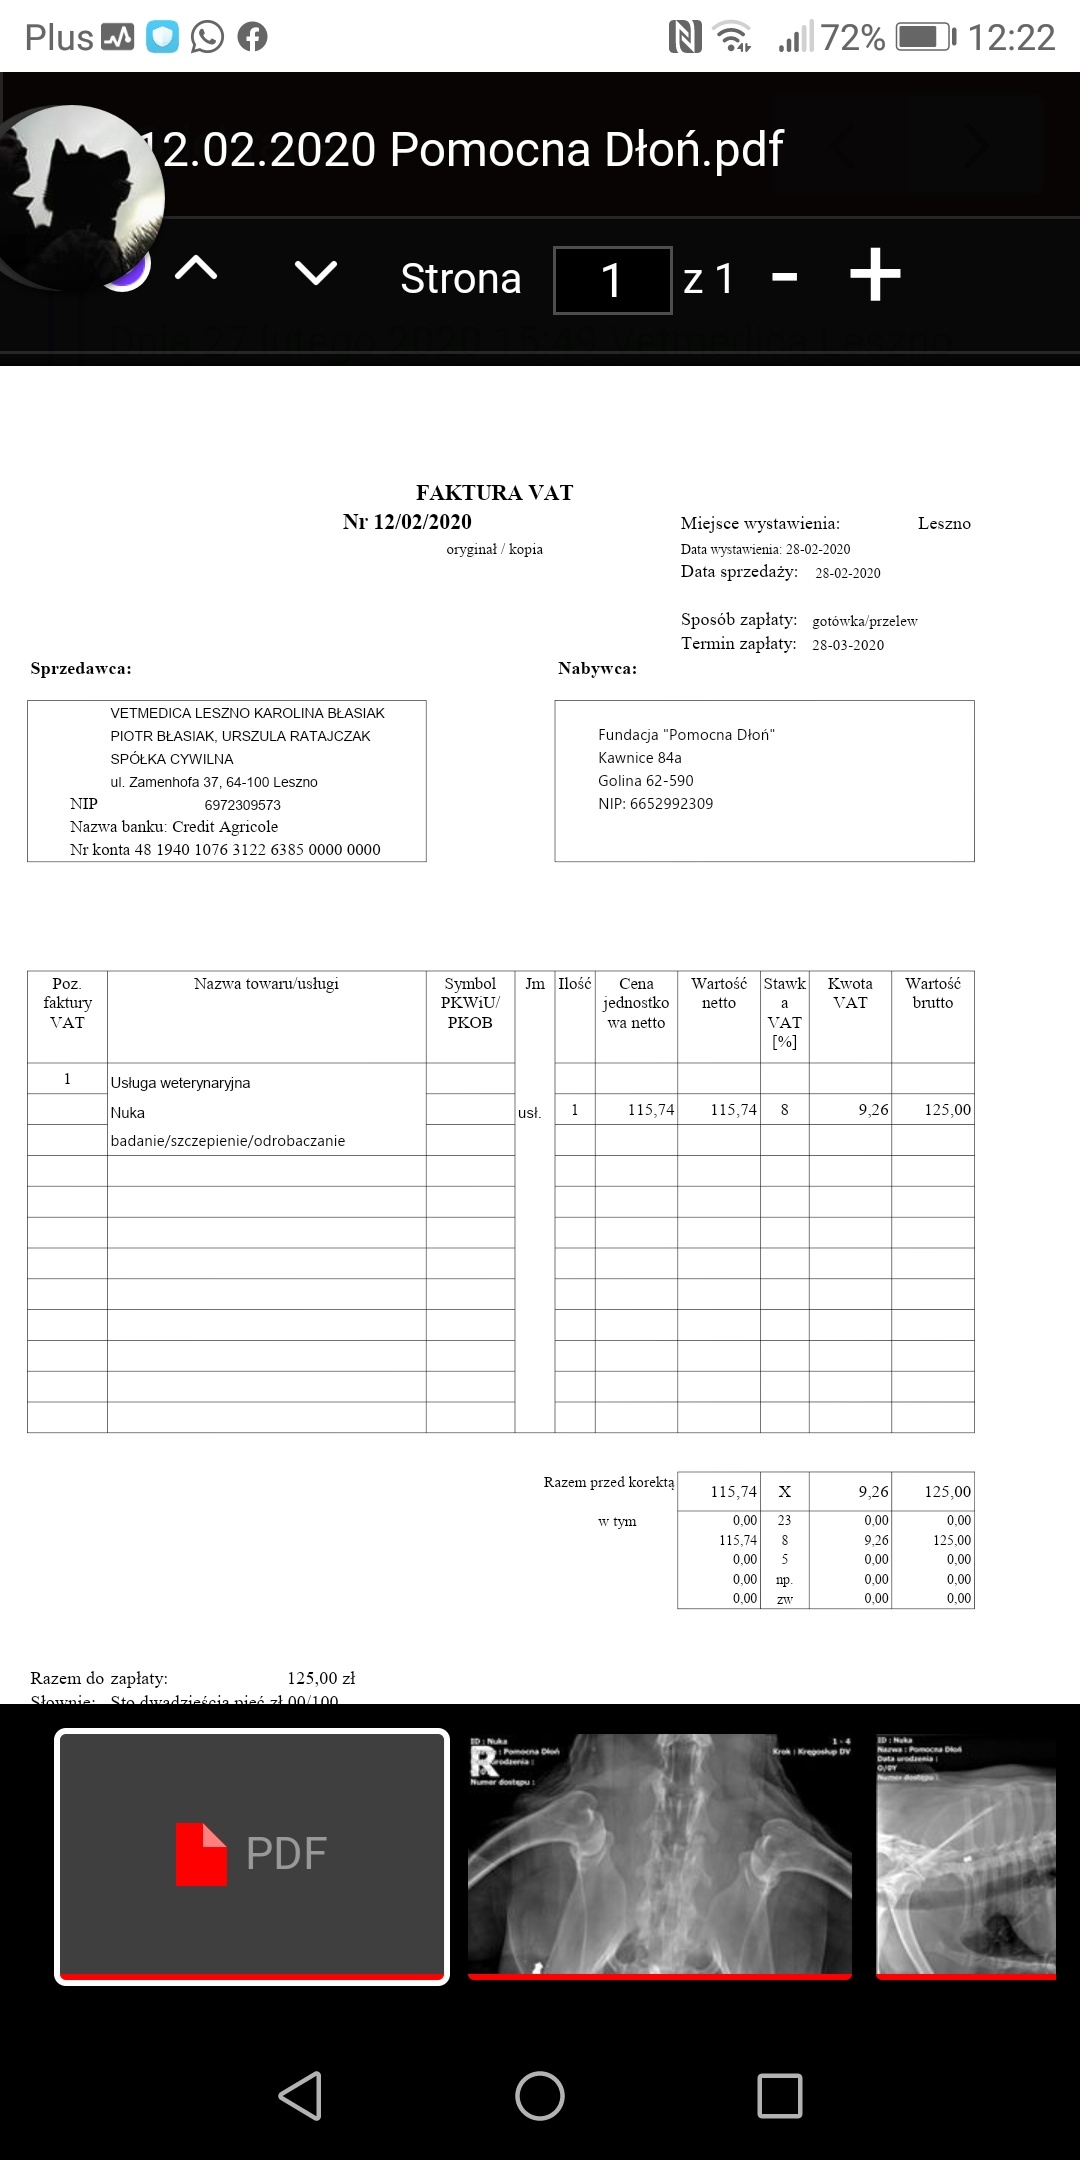

NA zdj fakturka jeszcze za badania i szczepienie